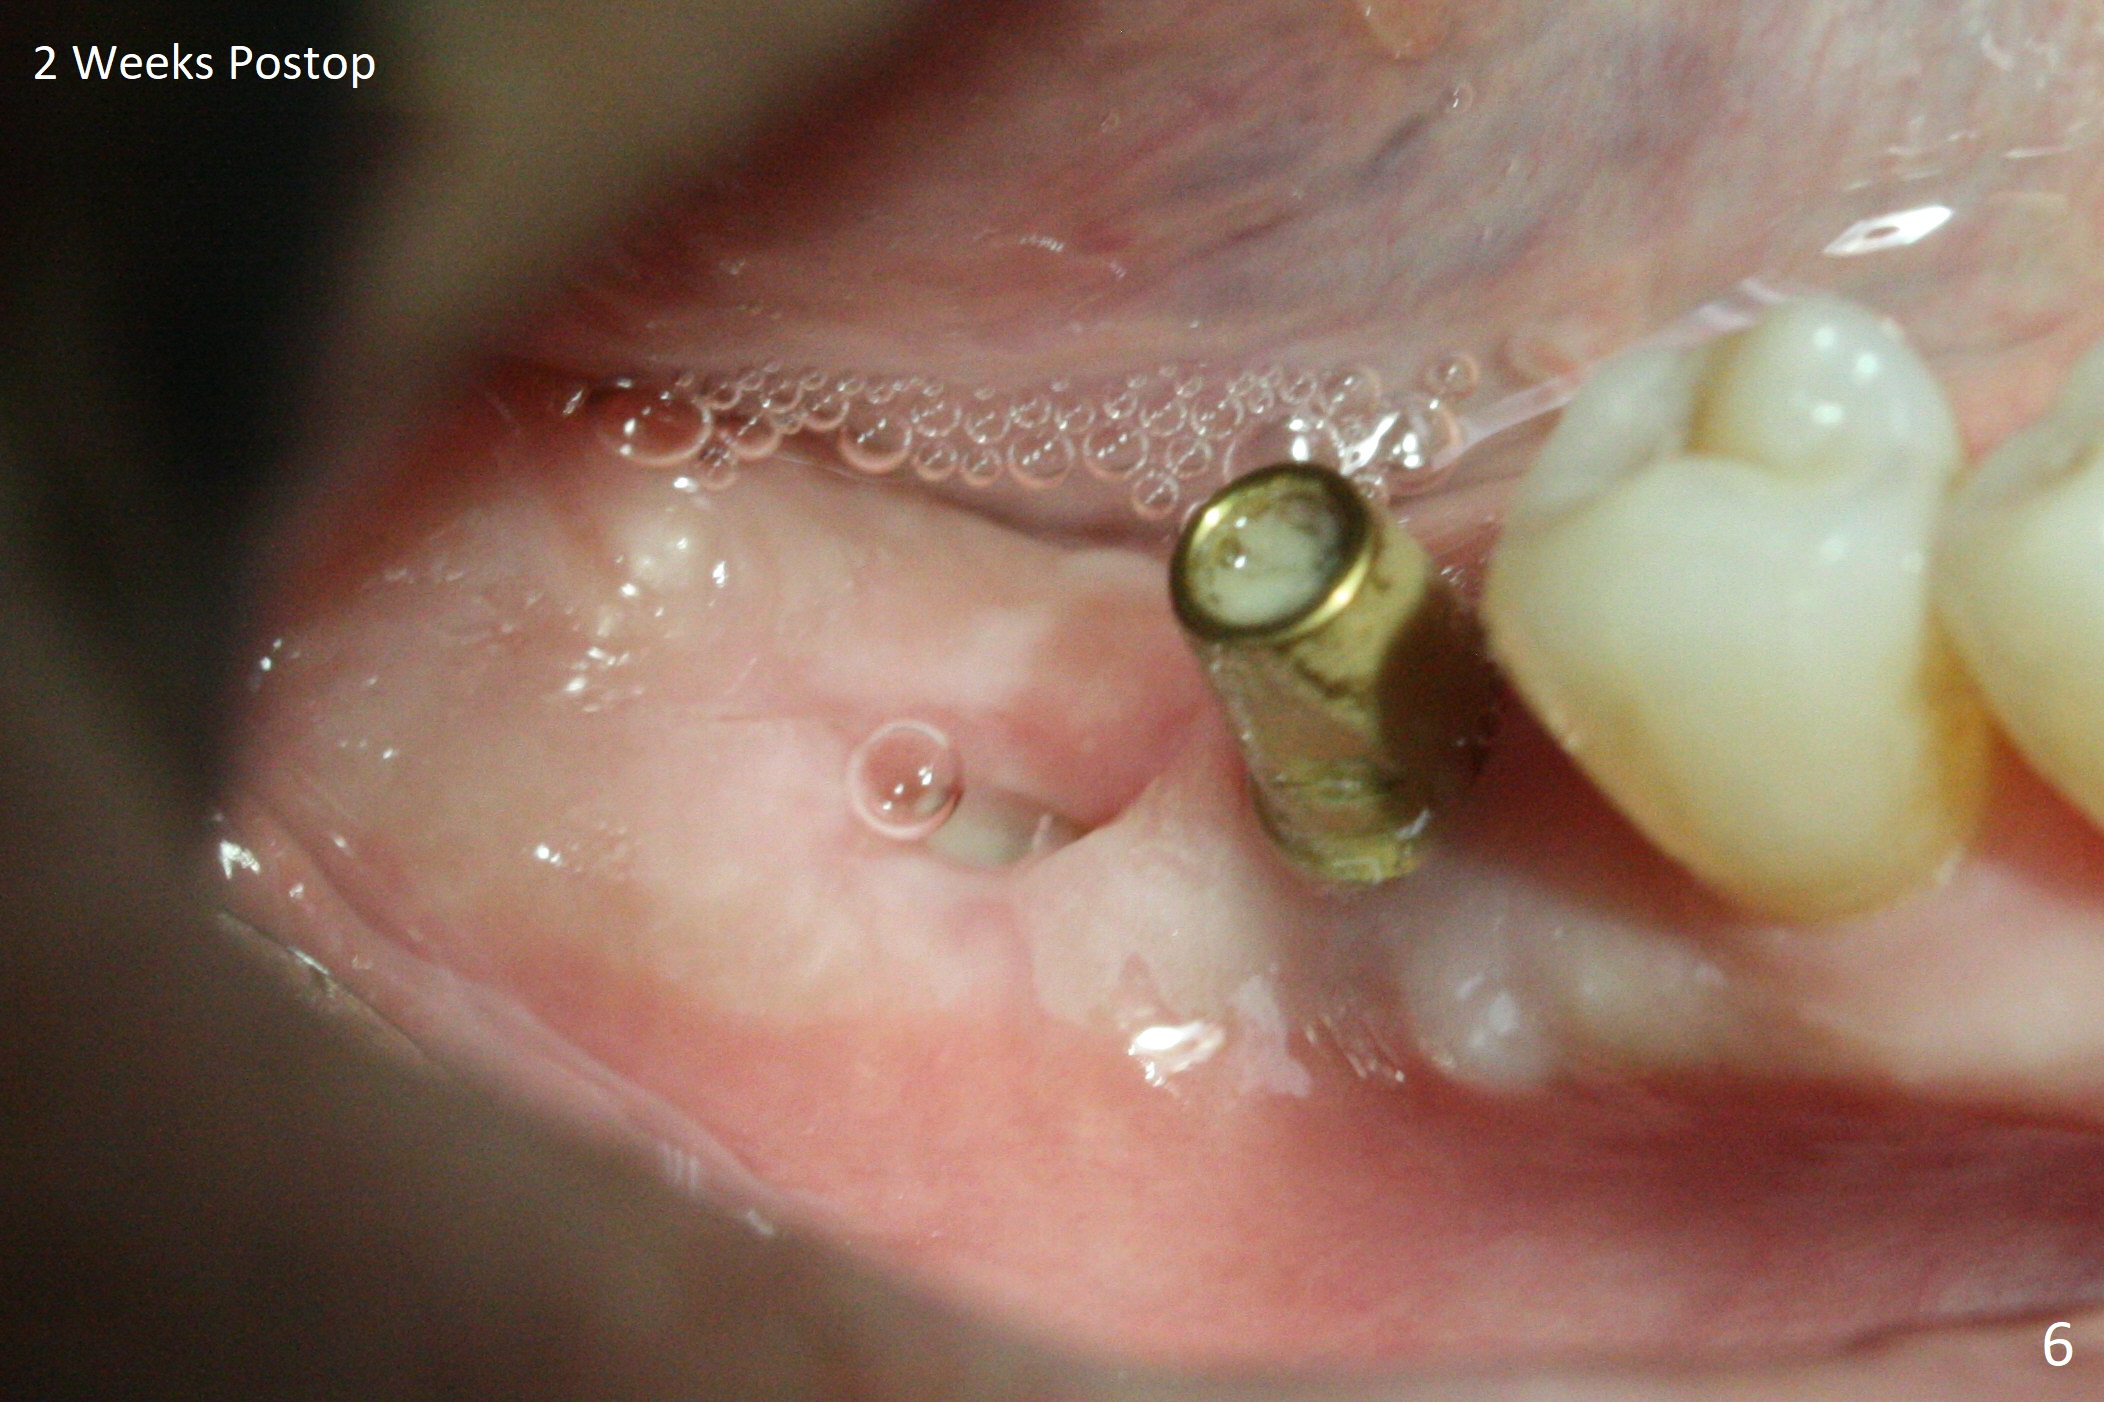

Osteotomy at the sites of #30 and 31 is initiated with Magic Split, followed by Magic Expanders (3.0 and 3.8 mm) at #31.  Initial depth of osteotomy is 13 mm with 2.2 mm drill (Fig.1).  After adjustment of the trajectory at #31 (Fig.1 arrow) and deepening the osteotomy by 2 mm, dummy implants are placed with stability (Fig.2).  Following increase in osteotomy at #31, the larger implant in fact loses stability (Fig.3).  The loose implant is pushed distal (Fig.4 arrow) with placement of autogenous bone mesial (*).  The stable implant at #30 (Fig.3) and its abutment (Fig.4) are used as a post to hold periodontal dressing, which covers the wound at #31 after placement of collagen plug and suturing.  In fact the same technique could be used when socket preservation was performed if an implant were placed at #30 at the same time.  When the periodontal dressing dislodges, the wound at #31 heals uneventfully (Fig.5,6).  The bone graft seems to remain in place 3 months postop (Fig.7).  The implant is uncovered with placement of a 6.8x7 mm healing abutment 4 months postop.  When a cementation abutment is placed and prepped, the buccal margin is much lower than the lingual (Fig.8 taken prior to cementation).  The patient enjoys mastication with the new implant crowns 3.5 months post cementation (Fig.9).